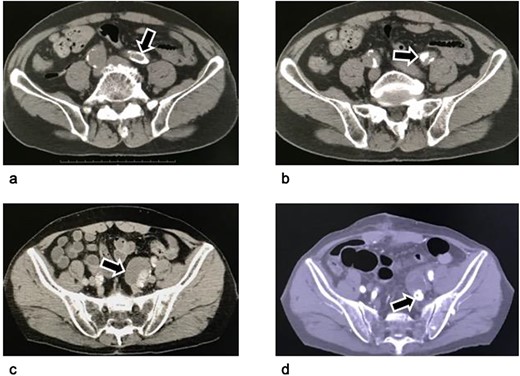

A 78-year-old man was referred to our facility for treatment of a left internal iliac artery aneurysm (36 mm in diameter on the left side) (Figure 1).

Computed tomography of an isolated internal iliac artery aneurysm. (a–c): Images before the operation: An isolated internal iliac artery aneurysm on the left with a diameter of 36 mm can be seen. The left common iliac artery and the neck of the left internal iliac artery aneurysm were severely calcified (arrows). (d) Image four months postoperatively: The aneurysm sac has become smaller because its wall was resected as much as possible. The vascular plug in the internal iliac artery is visible distal to the aneurysm (arrow).